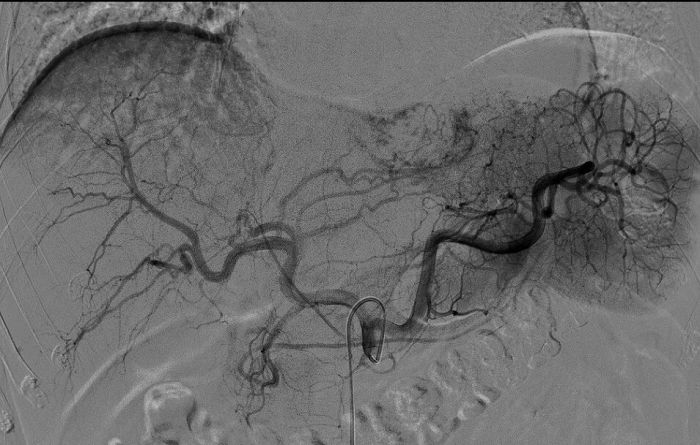

该患者5年前体检发现肝血管瘤,近期复查显示瘤体较前增大。为避免传统外科手术带来的较大创伤与较长恢复期,经德江县人民医院介入科团队评估,为其施行了经导管肝动脉栓塞术。手术仅通过右侧股动脉一个约2毫米的穿刺点,将微导管精准送至肝脏血管瘤的供血动脉,注入栓塞剂,使瘤体因缺血而逐渐萎缩,从而达到治疗目的。